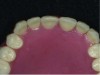

Fig 5. The final denture in the patient’s mouth.

Figure 5